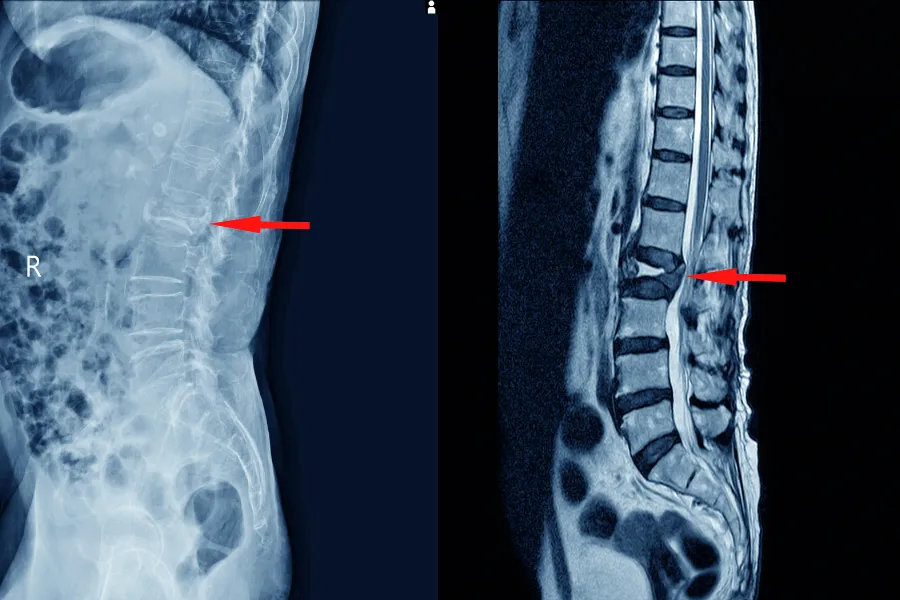

Діагностика стенозу хребетного каналу починається з ретельного клінічного огляду, який дозволяє оцінити неврологічні функції, зокрема силу м’язів, рефлекси, чутливість шкіри та характер рухових порушень. Проте вирішальну роль у підтвердженні діагнозу відіграють інструментальні методи, серед яких МРТ хребта є ключовим та найбільш інформативним.

Магнітно-резонансна томографія дає можливість отримати високодеталізовані зображення м’яких тканин, міжхребцевих дисків, зв’язок і нервових структур, які формують хребетний канал. За допомогою МРТ лікар може точно визначити ступінь звуження, побачити компресію спинного мозку або нервових корінців, відрізнити відносний стеноз від абсолютного і виявити супутні патології, такі як протрузії та грижі дисків, кісти, гіпертрофія зв’язок чи артроз. МРТ також дозволяє оцінити набряк, запалення та зміни в нервовій тканині, що неможливо побачити на інших видах обстежень.

У складних випадках також може призначатися комп’ютерна томографія, яка краще візуалізує кісткові структури й допомагає уточнити анатомію хребців. Іноді додатково проводять електронейроміографію для оцінки функції нервів, якщо симптоми не повністю корелюють з даними візуалізації. Такий комплексний підхід до діагностики дає можливість повністю зрозуміти причину стенозу, оцінити ступінь ураження та обрати оптимальну тактику лікування, орієнтуючись на індивідуальні особливості пацієнта.